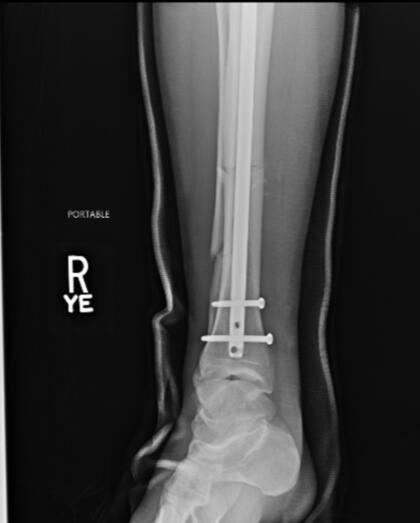

El sábado pasado, Chris Weidman se rompió la pierna en pleno combate contra Uriah Hall. Cuando apenas habían pasado 17 segundos del primer round entre los luchadores de UFC, el neoyorquino de 36 años le lanzó una patada al jamaiquino de su misma edad y terminó tumbado en el piso con una fractura de tibia y peroné. Ahora, el peleador de artes marciales mixtas mostró cómo quedó tras pasar por el quirófano.

“Algunas radiografías antes y después de la operación”, escribió en Twitter, junto a un par de imágenes donde mostraba cómo tenía la pierna apenas fue hospitalizado y cómo le quedó tras la cirugía, donde le colocaron una serie de clavos.

En una entrevista con el medio norteamericano TMZ, Weidman contó que le pusieron una varilla de titanio a través de la tibia y dijo que también se le había roto el peroné. Tal lesión lo obligará a estar entre seis y 12 meses en reposo para poder volver a los entrenamientos.